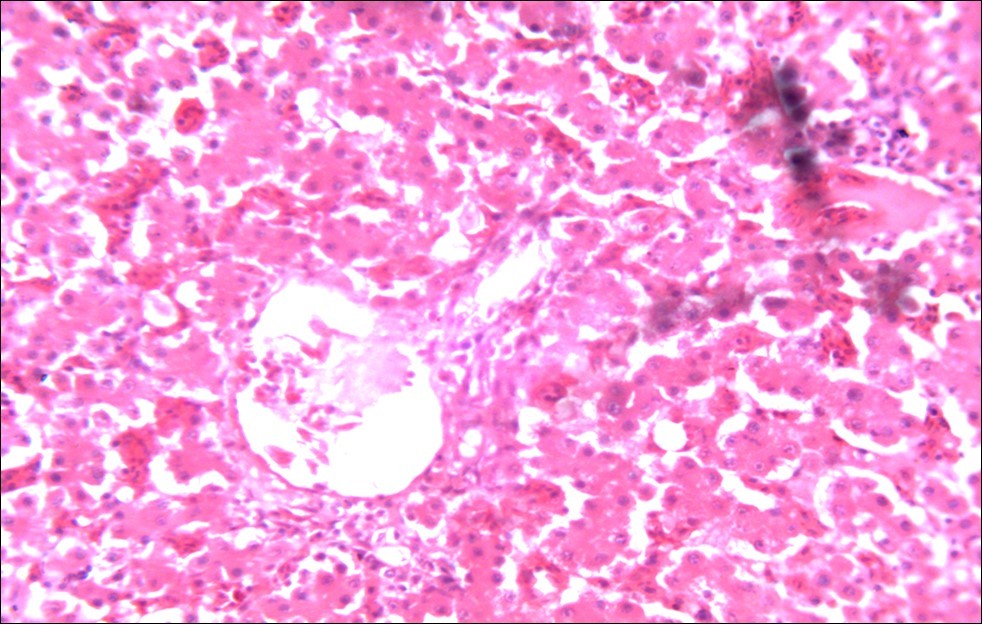

Figure 5.Photomicrograph of caecum of chick administered 20000 Oocysts of Eimeria tenella and treated with NeemAzal® Oil showing generalized degeneration of the caecal glands (d), moderate Ocysts presence (o) with fibrosis (f) X250 (H & E).

In addition, the generalized degeneration of the caecal glands, moderate numbers of gametocytes within the glandular regions with fibrosis which underscores reparative process in response to injury evoked by coccidiosis in the chicks which was perhaps brought about by the antioxidant and chemotherapeutic effect of NeemAzal®. The observed increase in RBC and hemoglobin concentration (Table 1) is indicative of the erythropoieticability of NeemAzal®, which is beneficial since the Eimeria parasite in the epithelia of the intestines causes bloody diarrhea and consequently anaemia. This finding is in consonance with 15 who reported an anti-anaemic effect of Khaya senegalensis on phenyl hydrazine-induced anaemia in rats. If the results of this study are juxtaposed with the results of the previous studies on potent antioxidant, hepatoprotective and mitigative role of methanolic extracts of Azadirachtaindica,in both natural and experimental infection with Eimeria species and can be deduced that, NeemAzal® could be said to be a potent antioxidant, chemotherapeutic and tissue protective agent. This study also answered a question on further study advocated to determine the maximum safe levels of neem supplementation because the higher doses, due to its bitterness, may show adverse effects on feed intake which will change the performance parameters of birds (Figure 6 and Figure 7) . Light microscopic inspection of hematoxylin and eosin-stained sections revealed that the epithelial cells of the Cecum were infected by E. tenella(Figure 3 and Figure 4). The results of the safety study showed that exposure of chickens to NeemAzal® at 200mg/kg body weight did not alter the histoarchitecture of liver and kidney (Figure 6 & Figure 7) which is similar to the work conducted in the same environment by a group of Scientists 34. It is therefore recommended that NeemAzal® could be used as a coccidiostat to replace the expensive anti-coccidiostats in the market.

In this study, the reduction in oocyst count observed in the treated group was compared with amprolium could be attributed to the presence of a bioactive compounds azadiractin A which is known to bind membrane cholesterol, altering the integrity of the parasite membrane, resulting in loss of homeostasis and eventual death of the parasite 29]. Also, limonoids contained in NeemAzal® inhibit protein digestion and uptake of vitamins and minerals by the parasites in the gut 17. This action results in impaired nutrient utilization, reduced growth, and multiplication of the parasite which could contribute to the reduced oocyst count observed. Extracts of neem and mahogany when used individually have been reported to reduce oocyst count in avian coccidiosis 11,12. The observed reduction in oocyst count and the significant increase in weight gain of the birds when treated with NeemAzal®, as compared with the negative control group could probably be due to the inhibition of inflammation in the intestinal mucosa which is suggestive of an increased nutrient absorption across the intestinal wall and enhanced feed conversion ratio compared to the negative control this is in agreement with reports by Nwosu et al.12 and Biu et al.11 who also reported an increased weight gain and feed conversion ratio in birds treated with only Khaya senegalensis extracts and Azardiractaindica, respectively. The observed increase in RBC and haemoglobin concentration is indicative of the erythropoieticability of the NeemAzal®, which is beneficial since the Eimeria parasite in the epithelia of the intestines causes bloody diarrhoea and consequently anaemia (Table 1). This finding is in consonance with 15 who reported an anti-anaemic effect of Khaya Senegalensis on phenyl hydrazine-induced anaemia in rats. Neem has been shown to possess anti-anaemic properties in rats 14. The significant increase in mean weight gain in treated birds when compared to the negative control is possibly due to the inhibition of inflammation in the intestinal mucosa which is suggestive of an increased nutrient absorption across the intestinal wall and enhanced feed conversion ratio compared to the negative control. Nwosu et al.12 and Biu et al.11 reported an increased weight gain and feed conversion ratio in birds treated with only Khaya Senegalensis andAzadiractaindica extracts, respectively. In a similar study, Neem acts like toltrazuril exhibiting anticoccidial. In addition, exposure of broiler chickens to 20000 Oocysts of Eimeria tenellacaused generalized degeneration of the caecal glands with massive Oocysts and gametocyts within the caecal glands with fibrosis (Figure 3, Figure 4 & Figure 5), however, broiler chickens treated with NeemAzal® post exposure to 20000 Oocysts of Eimeria tenella, shows equal numbers of caecal tissues with non-observable histopathological lesions (Figure 4), possibly due to the antioxidant and anti-coccidian effects of NeemAzal®. The exact mechanism of action of neem against coccidian parasites is unknown, but a report by the National Research Council 1992 30, suggested that aqueous neem leaf extract, when taken orally, produces an increase in red cells, white blood cells and lymphocyte counts thus enhancing the cellular immune response, increasing antibody production and so most pathogens can be removed before they cause the symptoms associated with disease this was in agreement with this study as seen in Table a remarkable increase of the RBCs.